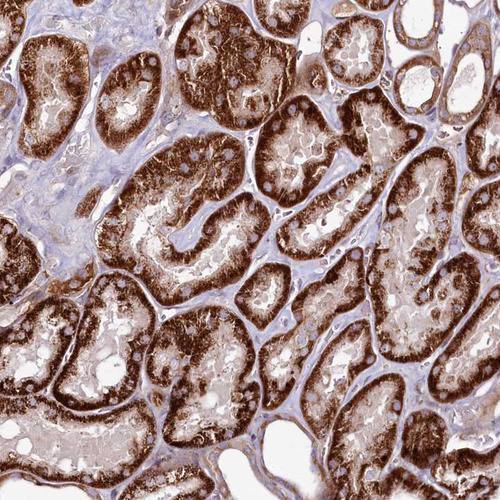

Immunohistochemical staining of human liver shows moderate granular cytoplasmic positivity in hepatocytes.